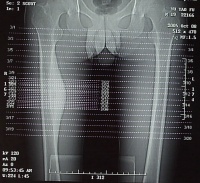

大腿

的X光片

人

下肢

从臀部到膝盖的一段,也叫股。